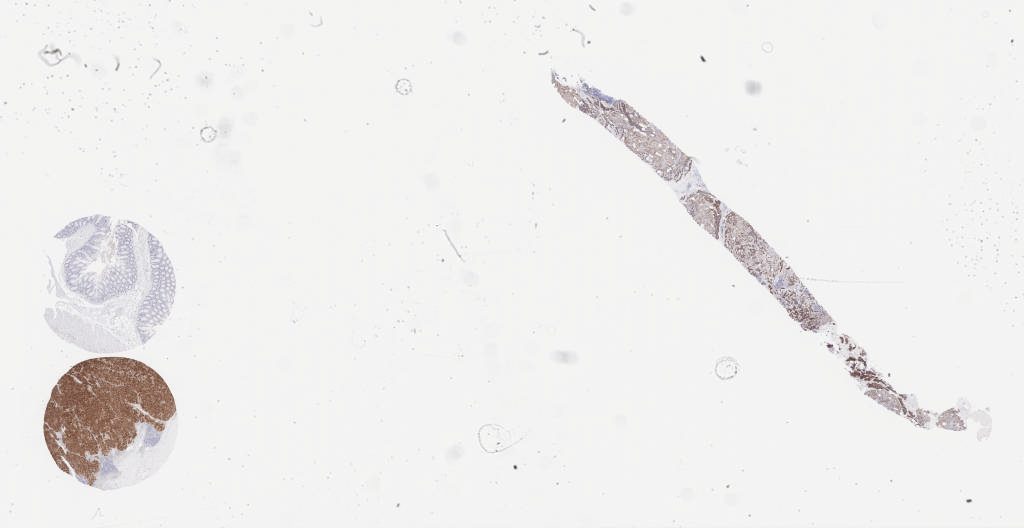

dc63ad8e-64b3-7901-4643-7102227c0f05_121412.svs

61006

x

46066

@

40X